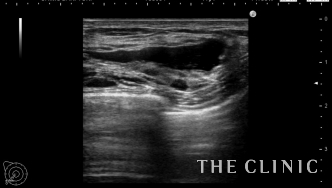

エコーで確認するとかなり厚い被膜が形成されています。

アクアフィリングは生理食塩水で溶解されるとのことで、エコー下に生理食塩水を注入しました。

なかなか溶解できず、ヒアルロニダーゼも追加してなんとか溶解除去することができました。